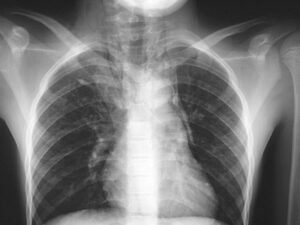

¿Cuáles son los síntomas de asma? El asma provoca la inflamación del recubrimiento interno de los bronquios y la contracción de los músculos que rodean las vías respiratorias, lo que genera síntomas como tos, silbido al respirar (sibilancias), dificultad para respirar y sensación de opresión en el pecho.

Según información de Medline Plus, el asma es una enfermedad crónica que provoca que las vías respiratorias de los pulmones se hinchen y se estrechen.

Esto hace que se presente dificultad para respirar como sibilancias, falta de aliento, opresión en el pecho y tos:

“El asma es causada por hinchazón o inflamación de las vías respiratorias. Cuando se presenta un ataque de asma, el recubrimiento de las vías respiratorias se inflama y los músculos que las rodean se tensionan”.

Dicho estrechamiento reduce la cantidad de aire que puede pasar por estas.